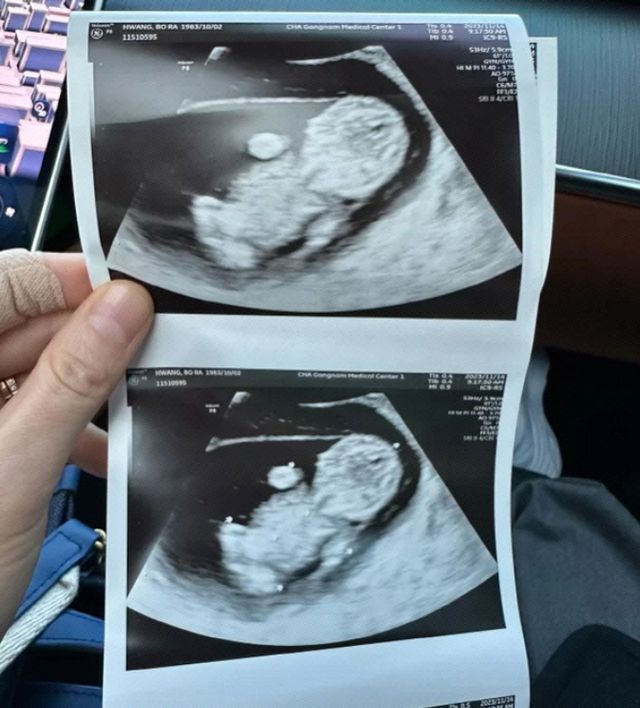

이번 달 출산을 앞둔 배우 황보라가 최근 자신의 유튜브 채널 영상에서 태아가 역아라는 소식을 듣고 걱정 하는 모습을 보여 시선이 쏠리고 있습니다.

지난 2024년 5월 12일 유튜브 채널 '웤톸'은 황보라의 임신 토크 '오덕이 엄마' 열아홉번째 에피소드 '임신 33주 차 황보라, 오덕이가 역아라구요...?'를 공개했습니다.

배우 황보라는 임신 30주 차에 병원을 찾았는데 백일해 주사를 맞고 태아 상태를 검진하기 위함이었습니다. 의사는 황보라의 태아 검진 중 "거꾸로 뒤집혔다"라며 태아가 역아 상태가 됐음을 알렸고 이에 황보라는 "바뀌어야 하는 거 아니냐, 지금 역아인 거냐"라며 걱정했습니다.

이후 상담 시간에 황보라가 "애가 또 거꾸로 돼 있다는데 왜 갑자기 그렇게…지난번에는 괜찮았는데"라며 걱정하자, 의사는 "아기 마음이다, 여기 있고 싶으면 여기 있는 거다, 이유가 있는 게 아니라, 거꾸로 있어도 수술을 하면 된다"라고 해 황보라를 안심시켰습니다.

3주가 지난 뒤 다시 검진을 받은 황보라는 역아 상태였던 태아의 머리가 다시 밑으로 왔다는 소식을 듣고 "다행이다"라며 안심했습니다. 발달도 양호했습니다. 전문의는 "지금 2.2㎏인데, 걱정 안 해도 되는 몸무게"라고 설명했습니다.